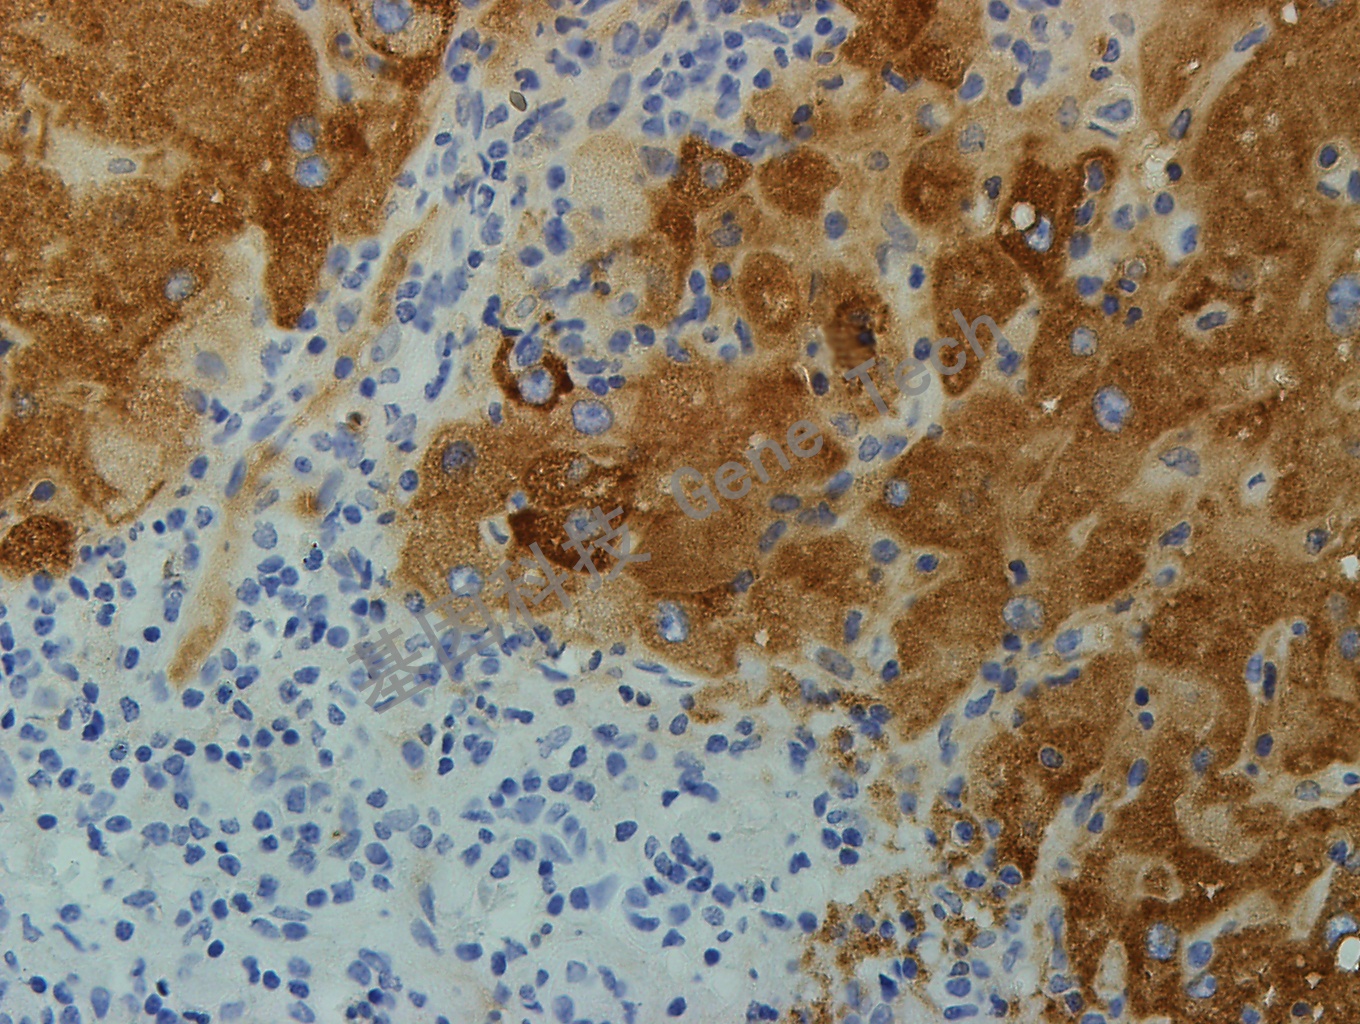

乙肝石蜡切片,用 HBsAg(GT2224)染色,细胞浆阳性,DAB 显色。